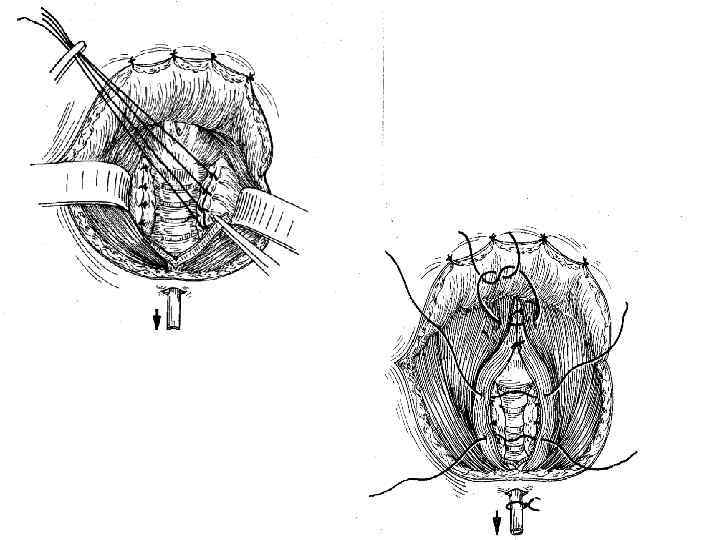

Лечение -Субтотальная тиреоидэктомия с ревизией л/у и удаление их при выявлении метастазов ( 1 -2 стадия при папиллярных и фолликулярных формах рака) -Комбинированная терапия при 3 стадии: - предоперационная гаммотерапия - субтотальная или тотальная тиреоидэктомия с фасциальнофутлярным иссечением клетчатки с обеих сторон -при отдаленных метастазах назначают 131 йод Прогноз: -Благоприятный при папиллярных и фолликулярных формах рака -Не благоприятный при солидных и недифференцированных формах рака

Лечение -Субтотальная тиреоидэктомия с ревизией л/у и удаление их при выявлении метастазов ( 1 -2 стадия при папиллярных и фолликулярных формах рака) -Комбинированная терапия при 3 стадии: - предоперационная гаммотерапия - субтотальная или тотальная тиреоидэктомия с фасциальнофутлярным иссечением клетчатки с обеих сторон -при отдаленных метастазах назначают 131 йод Прогноз: -Благоприятный при папиллярных и фолликулярных формах рака -Не благоприятный при солидных и недифференцированных формах рака